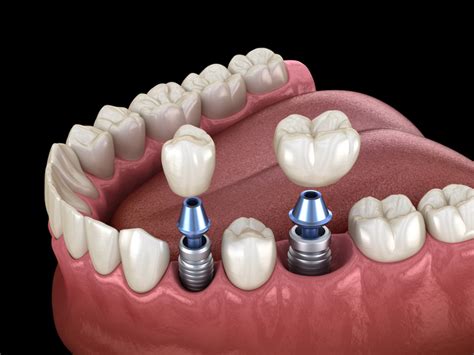

En los últimos años, la Implantología se ha convertido en una alternativa terapéutica imprescindible en la Odontología moderna. Los avances más destacados son en el diagnóstico y planificación de los casos, la mejora de la técnica quirúrgica y el control de la periimplantitis; todo ello de la mano de las nuevas tecnologías CAD/CAM.

La Implantología se encuentra en un momento magnífico, siendo una de las disciplinas de la Odontología que más ha progresado en los últimos años. La industria y los profesionales se han volcado en el avance de la misma de manera continuada.